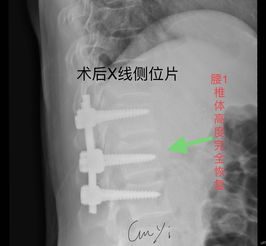

手術(shù)大致分為后路、側路、前路3個(gè)途徑。以往的手術(shù)常選擇后路的椎板減壓、探查+內固定,但后來(lái)逐步發(fā)現后路手術(shù)在很多情況下難以恢復脊柱的正常形態(tài)及穩定性,對來(lái)自前方的壓迫不易解除,長(cháng)期隨訪(fǎng)又發(fā)現了內固定失效、融合失敗、脊柱不穩、畸形愈合等情況;而且脊柱的后路內固定術(shù)須通過(guò)前柱的承重來(lái)實(shí)現其張力帶作用,抵抗牽張力和彎曲力矩,因此,前方支撐系統不可或缺。

由于X線(xiàn)檢查技術(shù)的進(jìn)步,特別是CT、MRI的應用,使人們確信脊柱骨折中脊髓神經(jīng)所受的打擊或壓迫大多來(lái)自硬脊膜前方,施行前路減壓術(shù)有了肯定的理由。但是前路手術(shù)因為涉及胸、腹腔臟器及重要血管等結構較多,手術(shù)難度較大,術(shù)后并發(fā)癥多,不僅對病人的全身、局部情況要求較高,而且也要求醫生掌握扎實(shí)的基礎理論和豐富的臨床經(jīng)驗,具備熟練的手術(shù)技巧。

不少醫生因此裹足不前,致使一些適合前路手術(shù)的病例被施行了后路手術(shù)。泉州市第一醫院骨科在胸腰椎骨折脫位伴截癱的診療上積累了豐富的經(jīng)驗,近年來(lái)逐步開(kāi)展前路手術(shù),取得了良好療效,技術(shù)日趨簡(jiǎn)潔、熟練。

胸腰椎前路內固定技術(shù)的應用使病灶得到清除、脊髓獲得減壓、脊柱得到即刻穩定,這樣一方面為病人術(shù)后早期離床活動(dòng)、早期康復提供了可能性,另一方面也為神經(jīng)功能的保護或恢復創(chuàng )造了必要條件;其合理性和臨床效果逐步得到了公認。 但前路手術(shù)無(wú)法探查脊髓、馬尾損傷的情況并給于必要的處理,因此把握好前路手術(shù)的適應證是臨床取效的關(guān)鍵,以下幾點(diǎn)基本達成共識:胸腰椎骨折或骨折脫位伴不全癱,確證在硬脊膜前方有壓迫存在;經(jīng)過(guò)脊髓造影、MRI或臨床神經(jīng)學(xué)體征可判斷,除硬膜前受壓外,馬尾、脊髓本身并無(wú)需探查及修復時(shí),必須致力于前路減壓;脫位已超過(guò)2~3周者,后路手術(shù)已難以復位者;若伴不全癱需行減壓術(shù),亦宜選用前路減壓。